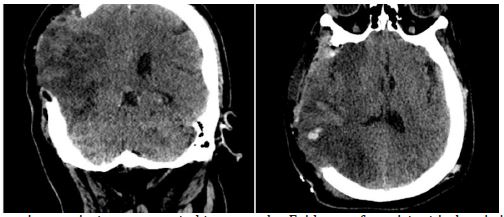

Twenty-four hours post-admission, his neurological status worsened (GCS decreased by 4 points), and a CT scan showed a significant midline shift. A right-sided frontotemporoparietal decompressive craniectomy was performed. Postoperatively, his GCS improved to 14 and motor strength improved to 3/5 on the Lovett scale (Figure 2). A Computed Tomography Angiography (CTA) performed 48 hours after surgery showed restored flow in the M1 and distal branches of the right MCA (Figure 3). A confirmatory cerebral angiogram at two weeks demonstrated patent flow throughout the MCA distribution (Figure 4).

Upon discharge, the patient had an ECG score of 15, a Karnofsky Performance Score of 70, and residual hemiparesis of 3/5. At a three-month follow-up, he had improved to a Karnofsky score of 90 and 4/5 strength in the left upper limb, with persistent left facial nerve palsy (Figure 5).

Figure 4: Cerebral angiography 2 weeks later, showing recanalization of the right MCA.